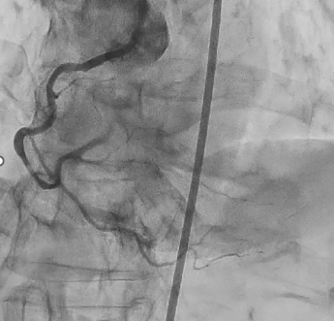

Coronary angiography revealed 100% occlusion of the right coronary artery (RCA) at segment #2, with collateral flow from the left anterior descending artery. The RCA was identified as the culprit lesion, and percutaneous coronary intervention (PCI) was planned. Engagement of the left coronary artery was achieved using a 7 Fr Launcher AL0.75 SH guiding catheter, and the lesion was crossed with a SION guidewire. A large amount of thrombus was observed in the coronary artery; therefore, thrombus aspiration followed by long balloon inflation using a 2.5 mm Ryusei balloon was performed. Although TIMI grade 1 flow remained in the #4PL branch due to residual thrombus, TIMI grade 3 flow was obtained in the #3–#4PD segments. The procedure was completed after intra-aortic balloon pump (IABP) insertion. After treatment for heart failure, coronary computed tomography performed on hospital day 21 showed thrombotic occlusion of the #4PD branch, for which a short course of direct oral anticoagulant (DOAC) therapy was initiated. Repeat coronary angiography on hospital day 33 demonstrated improved flow, although 99% stenosis persisted in the #4PL branch. As the RCA #2 lesion was identified as the culprit of acute myocardial infarction, a drug-eluting stent (Ultimaster Nagomi 3.0 ¡¿ 44 mm) was deployed in segment #2, and balloon dilation using an Agent 2.0 ¡¿ 30 mm balloon was performed for the #4PL branch, achieving successful revascularization.